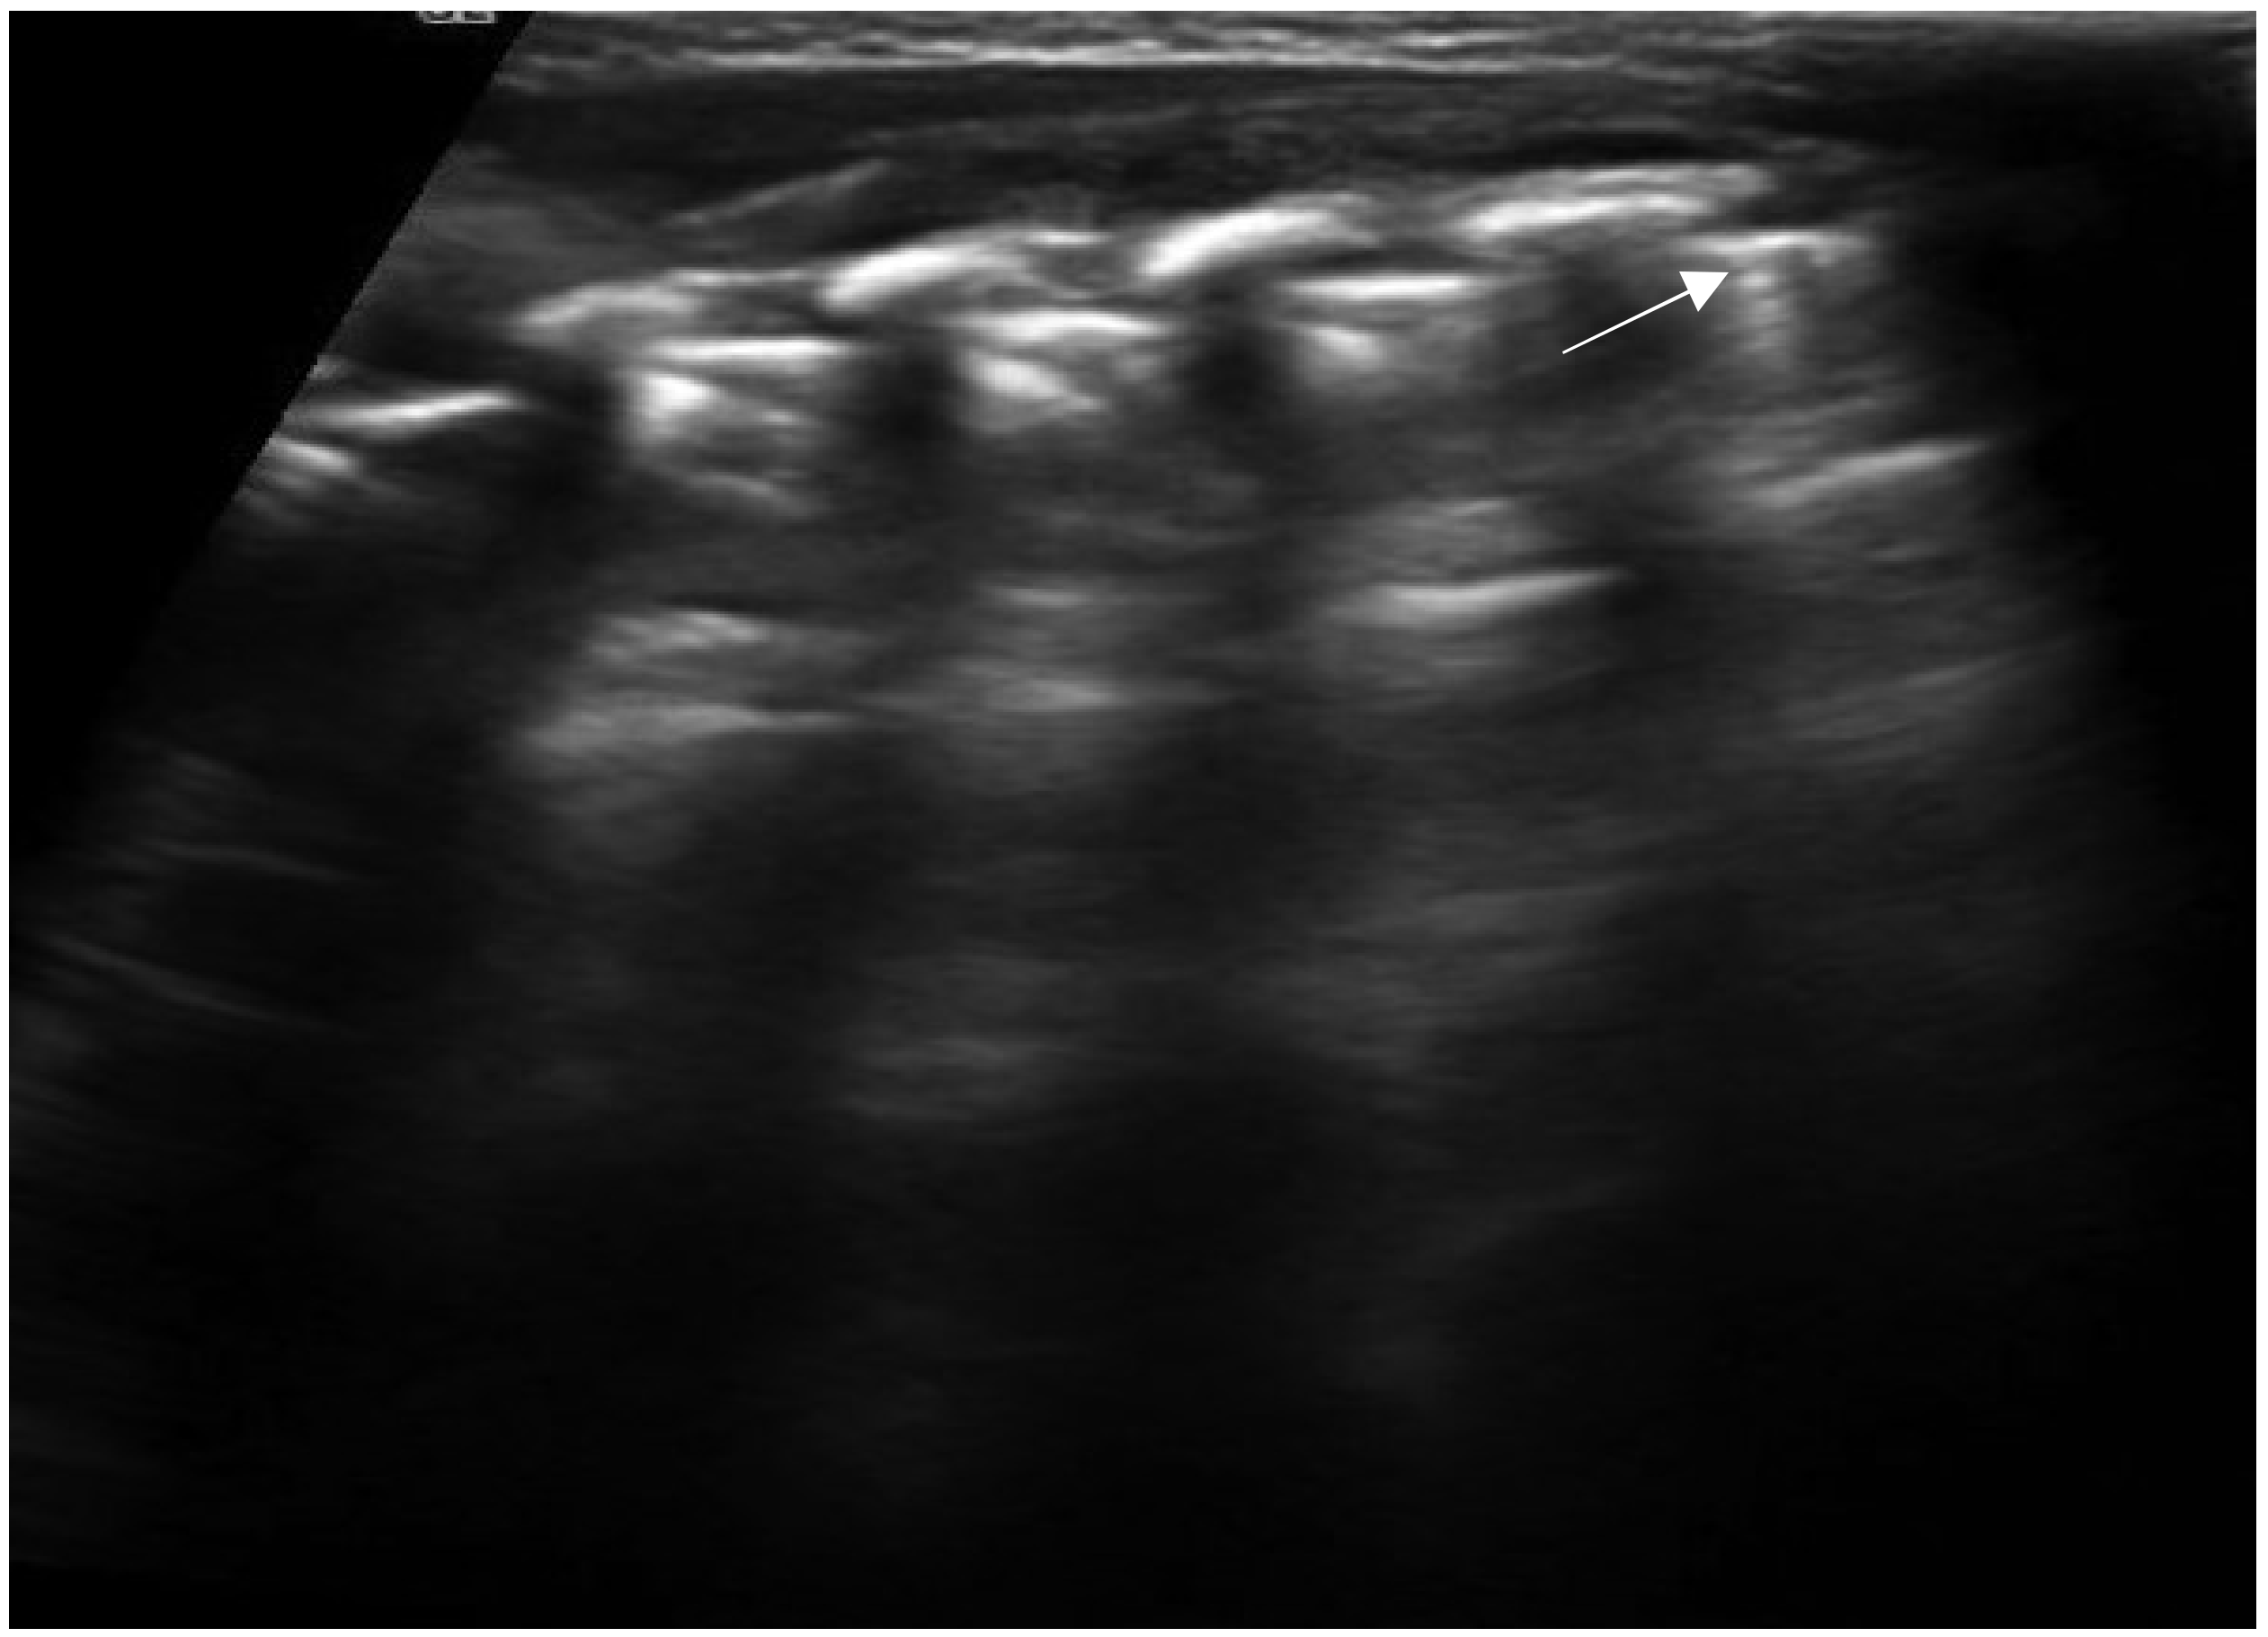

“A-lines” represent some of these artifacts that can be found in a completely healthy lung (Figure 1) [14]. They are horizontal echogenic lines equidistant and parallel to each other and the pleura, representing reverberations of the pleura itself that arise when the ultrasound beam reflects off of the pleura and partially reflects off of the probe face back to the pleura again before getting back to the machine instead of entering the probe. They are caused by the large difference in acoustic impedance between the pleura and the air contained in the lungs. The distance from each other is related to the distance between the pleural line and the skin surface, and their position does not change with respiratory acts.

Figure 1. Appearance of a healthy lung. White arrows show pleural and A-lines.